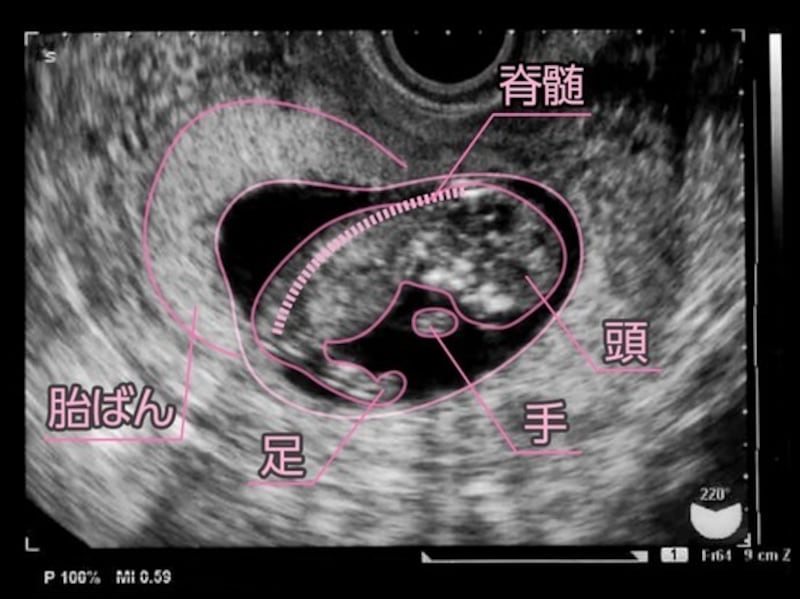

胆のう、膵臓(すいぞう)、肝臓、肺、甲状腺などの生命維持に必要な内臓は全てできてきました。脳はまだ小さいですが、出生時と同じ構造に発達しています。あくびもするようになります。手を開くこともでき、よく見ると、超音波で指が確認できるまでに。皮膚感覚は、とても敏感になっていて、温度や振動などを感じられるようになっています。

反射神経も発達し、膝を曲げたり伸ばしたりしています。これは生後に見られる歩行反射で、生まれるまでに十分時間をかけて完成されていきます。あくびや、指しゃぶりのような動きをすることもあります。